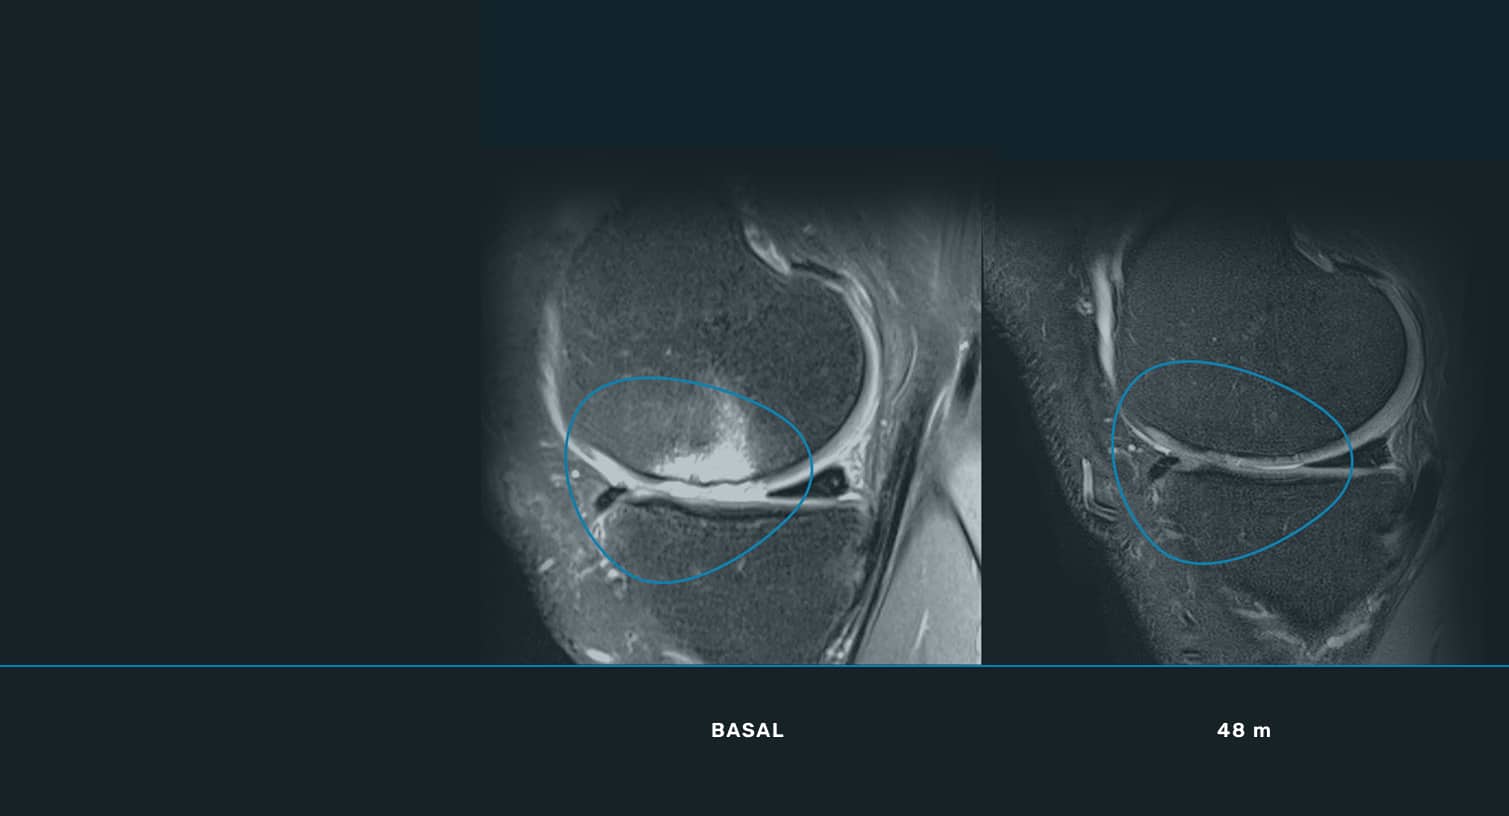

En ITRT hemos demostrado la viabilidad y seguridad de nuestras terapias mediante ensayos clínicos regulados y autorizados por la AEMPS (Agencia Española de Medicamentos y Productos Sanitarios). Una vez superado el ensayo clínico, la AEMPS autoriza el uso del medicamento en pacientes concretos, lo que permite ofrecer tratamientos personalizados con eficacia clínica y capacidad regenerativa demostrada.